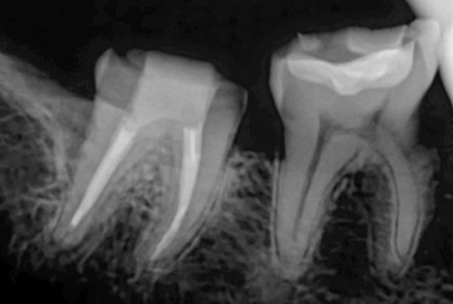

The images above show actual cases treated at SMILE FACE DENTAL CLINIC.

To a non-specialist, they may appear to be ordinary X-rays, but dentists can instantly recognize them.

They can appreciate both the complexity of the treatment and the care and precision involved.